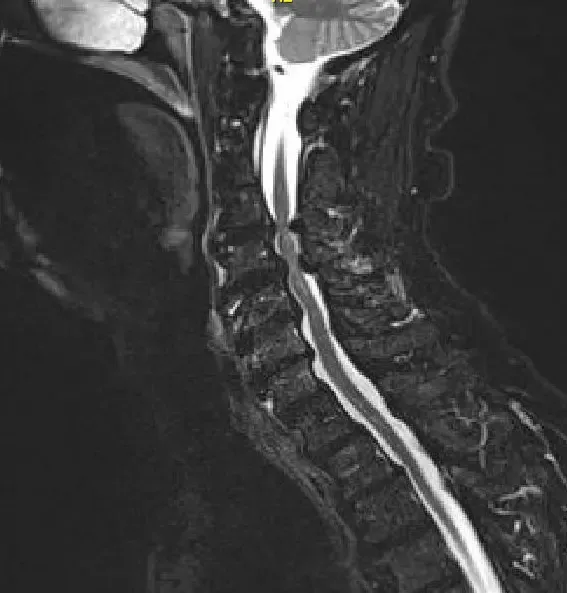

Imagen de la resonancia magnética T2 Corte sagital medio que muestra estenosis y compresión severa de la médula espinal en C3-4 y C 5-6 con enfermedad degenerativa de la articulación cervical